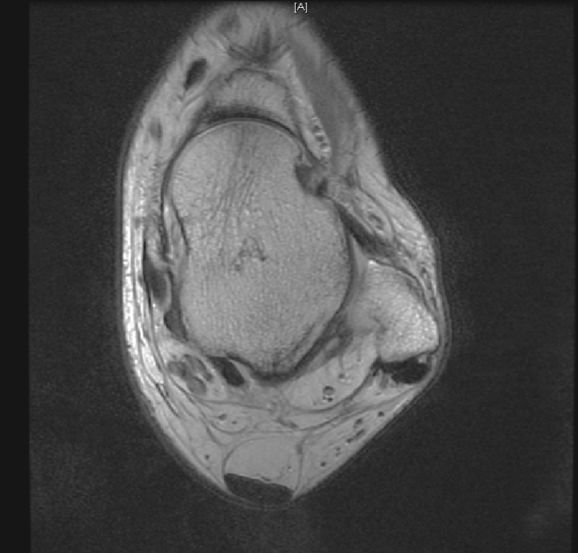

从这张片子我们可以看到正常的韧带结构,包括距腓前韧带,跟绯韧带,它是质地比较均一,T2相高信号,连续性良好,并且有良好的张力,从冠状位也可以看到跟绯韧带,在腓骨肌腱的深方,也是T2相跟T1相的低信号,有良好的连续性,张力也不错。